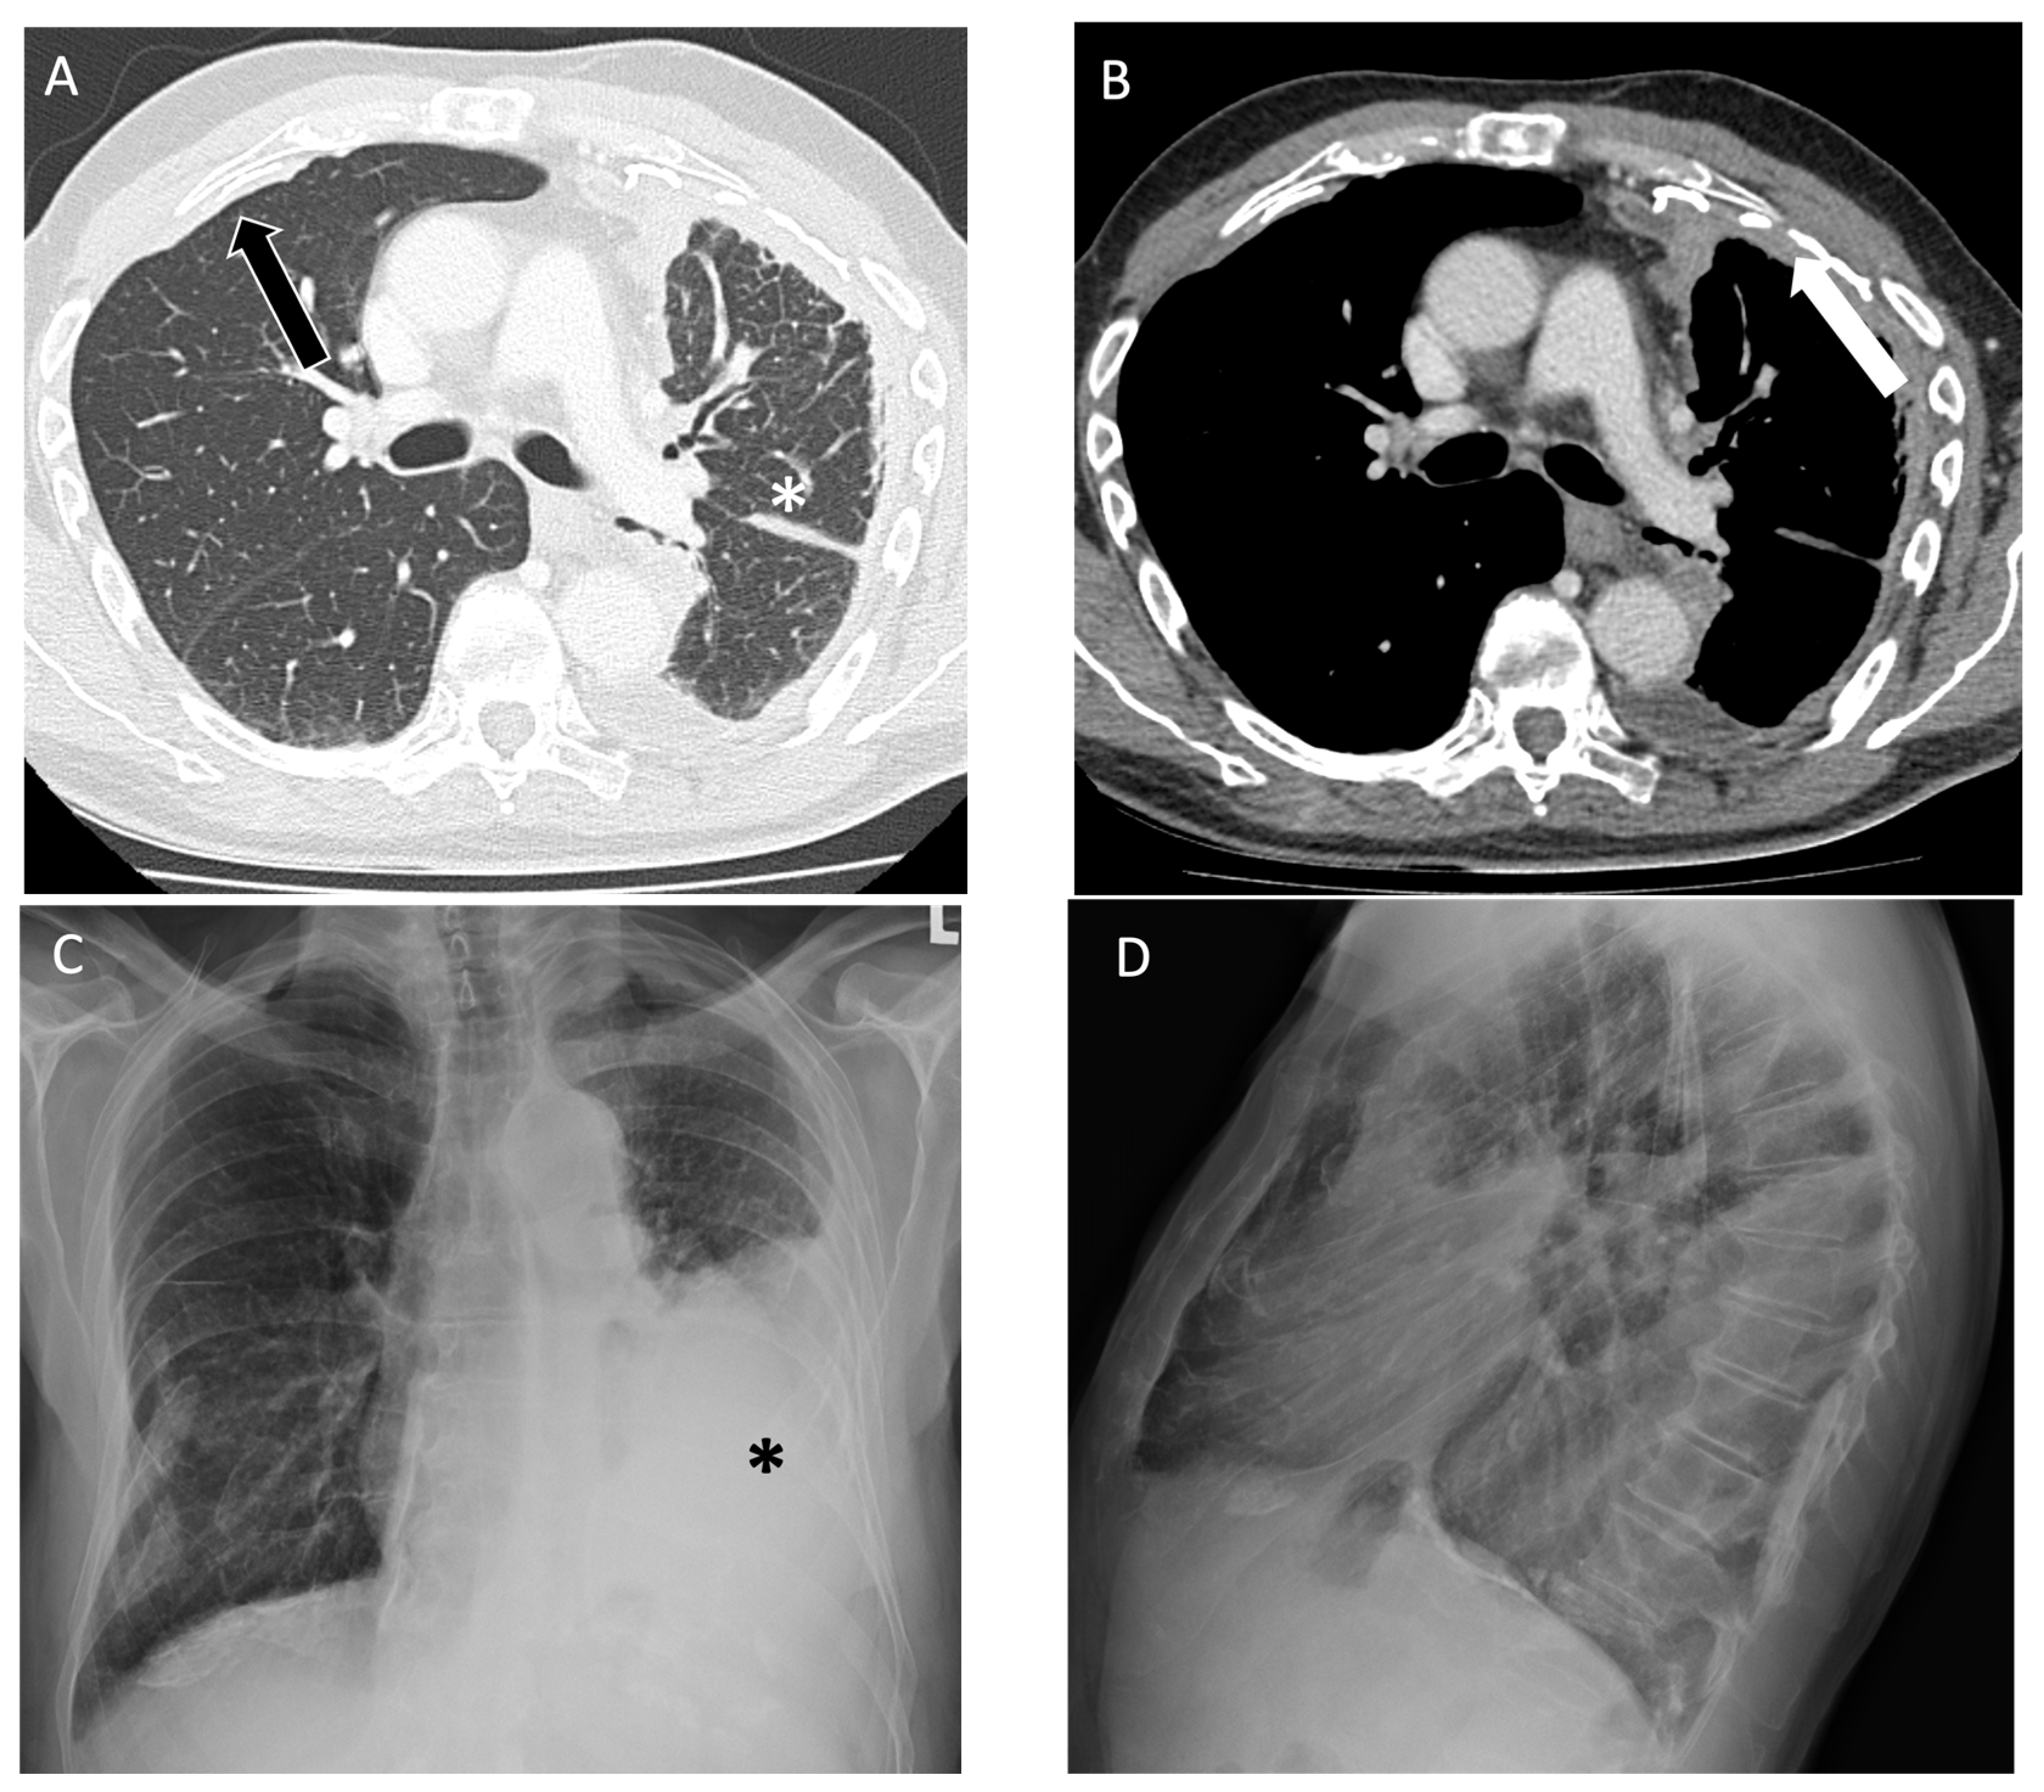

4.3. Asbestos-Related Lung Disease

| Asbestos-Related Lung Disease | Pleural effusion, smooth pleural plaques, rounded atelectasis [42,43,44] | Presence of smooth pleural plaques, often bilateral and along all pleural surfaces [45,46] |

| Mesothelioma | Various types of pleural thickening, interlobar fissure involvement, pleural effusion, pleural plaques [51] | Atypical pleural plaques, chest wall invasion [51] |